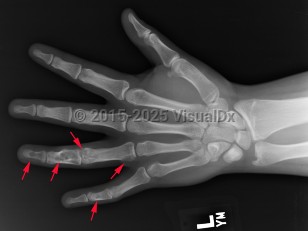

Imaging Studies image of Enchondroma - imageId=7900659. Click to open in gallery.  caption: '<span>Multiple enchondromas scattered throughout the 4th and 5th fingers.</span>'

Multiple enchondromas scattered throughout the 4th and 5th fingers.